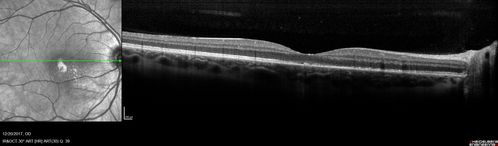

| Album name: | scohen125 / Unilateral Acute Idiopathic Maculopathy |

| Filename: | uaim2_brma_122017_001.jpg |